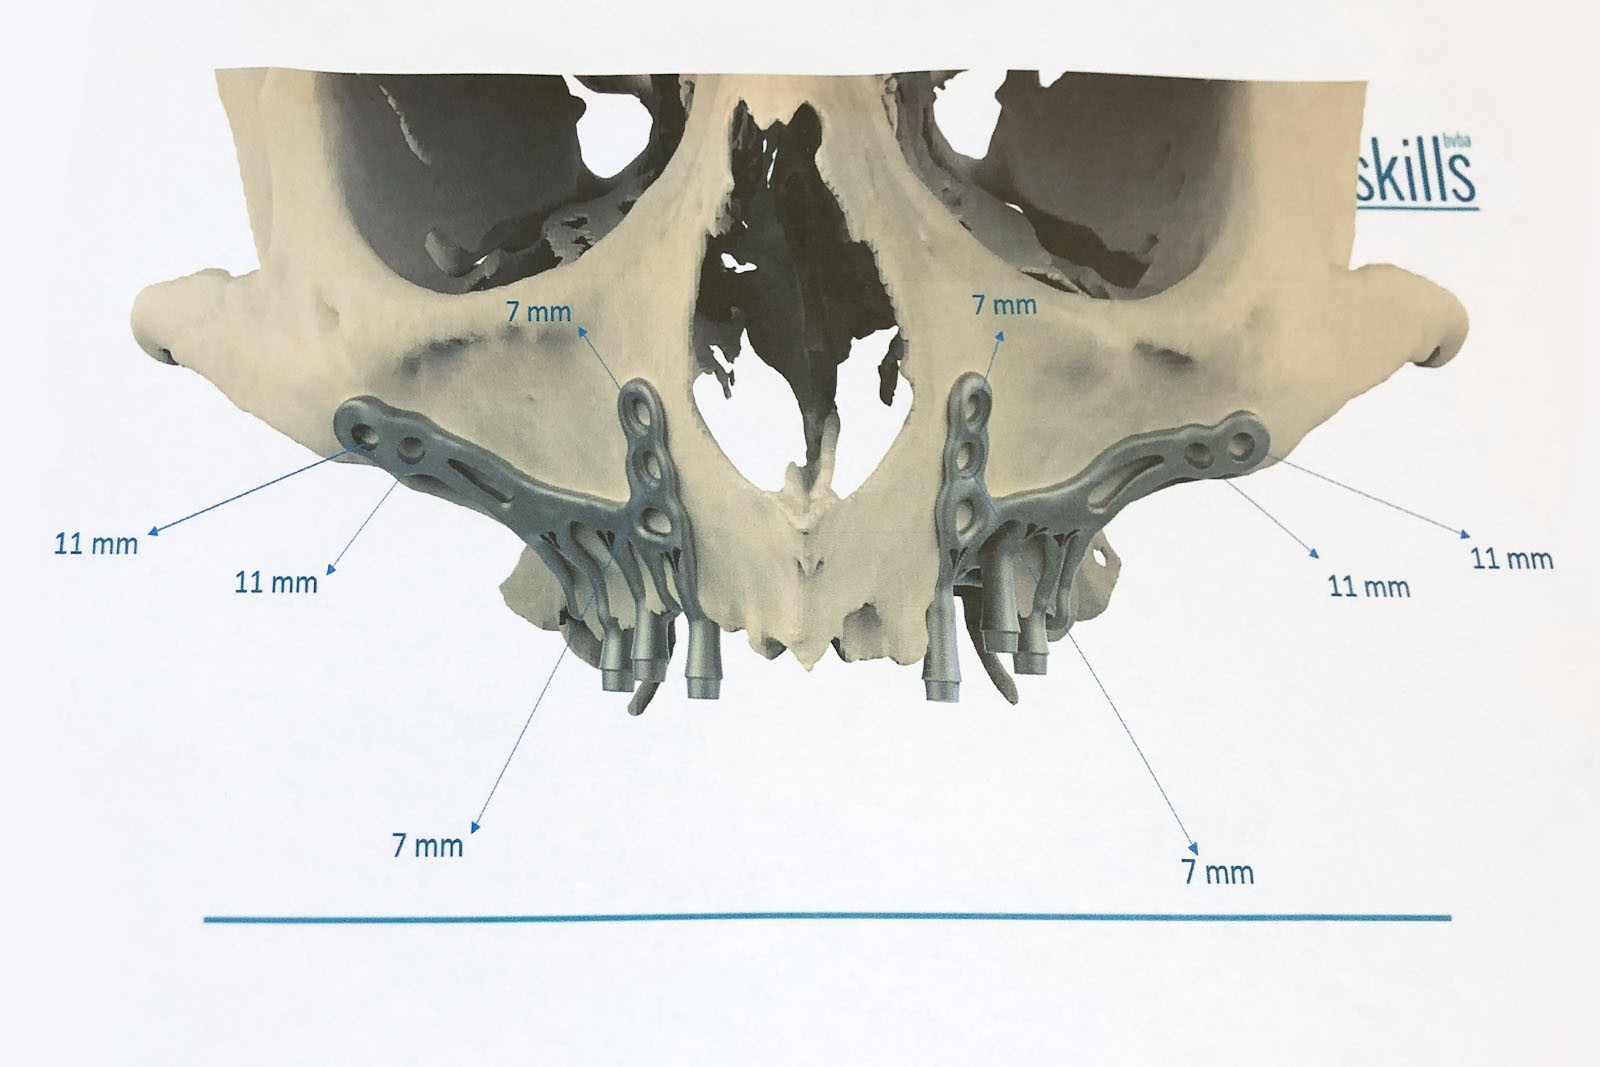

- System wytwarzanych indywidualnie podokostnowych implantów dla zanikłych kości szczęk Additively Manufactured Sub-Periosteal Jaw Implants NCBI Prof. Mourice Mommearts

- System implantów podokostnowych NCBI. Szczególny i innowacyjny system implantologiczny, który stanowi alternatywę dla zastosowania implantów Zygoma w sytuacji trudnych warunków kostnych przy bezzębiu szczęk. Przeznaczony jest tylko dla rozwiązań w zakresie górnego łuku zębowego. Metoda opatentowana przez prof. M. Mommeartsa z Kliniki Uniwersyteckiej w Brugge, Belgia.